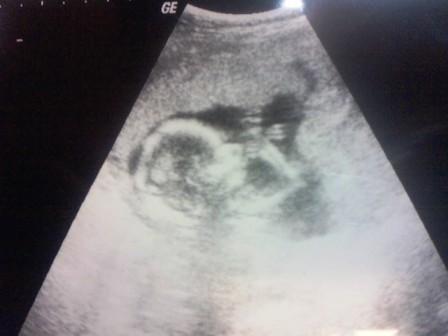

Végre megvolt az UH, szerencsére minden rendben a Picurkával a doki szerint is.

Az UH minősége nem volt valami jó, túl sokat nem láttunk, na meg persze se kép, se semmi.

De legalább láthattuk őt végre egy rövid ideig!

Magzat medencevégű fekvésben

BPD: 44 mm, HC: 160 mm, AC: 135 mm, FL: 30 mm.

Négyüregű szív, ritmusos szívműködés, épnek imponáló koponya és gerinc.

Ép hasi és mellkasi szervek, ép rekesz.

Ép, hiánytalan, hosszú csöves csontok.

Jó hólyagtelődés ábrázolódik, gyomortelődés sejthető.

Magzatvíz mennyisége átlagos, placenta a fundusban tapad

Magzati malformatiora utaló UH jel nem látható.